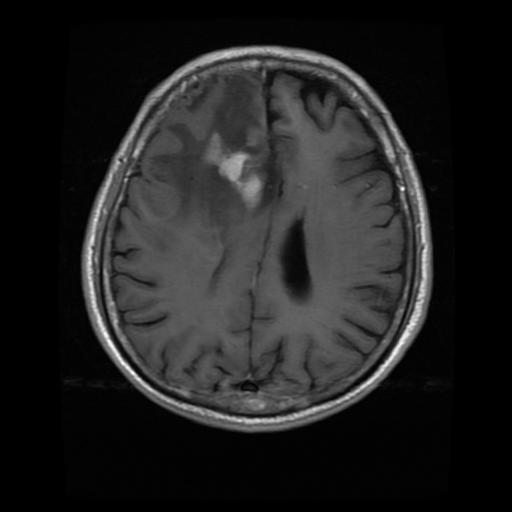

The input is MRI image. The images used here are in .jpg format. The MRI image dataset is obtained from publicly availablesources.Theseimagesaredividedintotwoyesand nofolders,eachcontainingimageswithandwithoutbrain tumors.

Fig - 1 : Flowchartofproposedmethod TheDatasetofbrainwithtumor: TheDatasetofbrainwithouttumor:

Infirststagewesuccessfullyconvertedtheinputimage(an OpenCV image) to grayscale using edge detection after applying pre-processing. Edge-based segmentation on an imageclassifiespixelsasedgeornon-edgedependingonthe filteroutput.Inregion-basedsegmentation,theimagewas subjected to regional maxima in order to group adjacent pixelswithsimilarvalues.TheCNNmodelwastrainedand testedbeforetheK-meanstechniquewasusedtoidentifythe regionofinterest(ROI),whichwasthenexaminedforthe presenceofatumor.

Fig - 2 : ImagePreprocessing OriginalImage CroppedImage Fig - 3:CNNmodelarchitecture Fig - 4:Trainingmodel